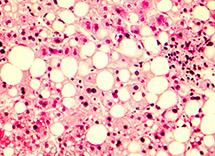

Среди всех гепатозов уверенное первенство держит жировая дистрофия – ее признаки обнаруживают в каждом четвертом результате биопсии, а у людей с излишней массой тела жировое поражение органа встречается почти в ста процентах случаев.

1. Признаки жировой дистрофии

При данном заболевании в клетках печени накапливается большое количество липидов и снижается ее способность функционировать в нормальном режиме. Обычно жировая дистрофия является сопутствующим заболеванием при сахарном диабете, нарушении обмена веществ и ожирении.

Диффузные изменения печени при данном заболевании выражены следующими признаками:

• увеличение размеров органа;

• изменение его формы;

• печень не деформируется при надавливании на нее датчиком;

• виден четкий рисунок вен органа;

• рисунок получаемый при диагностике грубый и плотный.

При жировой инфильтрации сначала отдельные участки, а потом, при запущенных заболеваниях, практически вся паренхима заменяется тканью по типу жировой.

Врачи при этом говорят, что у больного констатируются диффузные изменения печени по типу гепатоза.

Гепатозы – это общее название болезней печени, которые характеризуются тем, что здоровая ее ткань заменяется жировой и соединительной.

Сначала она еще может восполнять гибель здоровых клеток, но затем, из-за избытка токсинов, поступающих в организм, в печень начинают проникать жировые клетки, которые она не смогла уничтожить.

И вот уже их становится больше, чем здоровых, гепатоциты гибнут, печень становится больше за счет роста жировых клеток и начинает работать со сбоями. Жировые клетки при этом могут перерождаться в злокачественные.

Наиболее распространенными являются диффузные изменения печени по типу стеатоза. Стеатоз – это подвид гепатоза, характерный тем, что паренхима заменяется именно жировой, а не соединительной тканью.

Стеатоз диагностируется в том случае, если более 10% здоровой ткани печени превратилось в жировую.

Диффузный стеатоз считается коварным заболеванием – в течение очень длительного времени он ничем себя не проявляет, человек не испытывает никаких признаков болезни.

При этом печень постепенно меняет свою структуру, жировых отложений в ней становится все больше и больше.

Перестройка при жировом гепатозе

Возможно обнаружить с помощью УЗИ, если изменения ткани наблюдаются в более чем 1/3 органа. Для гепатоза печени характерно диффузное повышение эхогенности, но иногда оно остается нормальной. Также наблюдается увеличение печени, округление краев. Диффузные изменения паренхимы печени, такие как жировая инфильтрация лучше распознается при выполнении компьютерной или магнитно-резонансной томографии. Без своевременного лечения патология перетекает в цирроз.